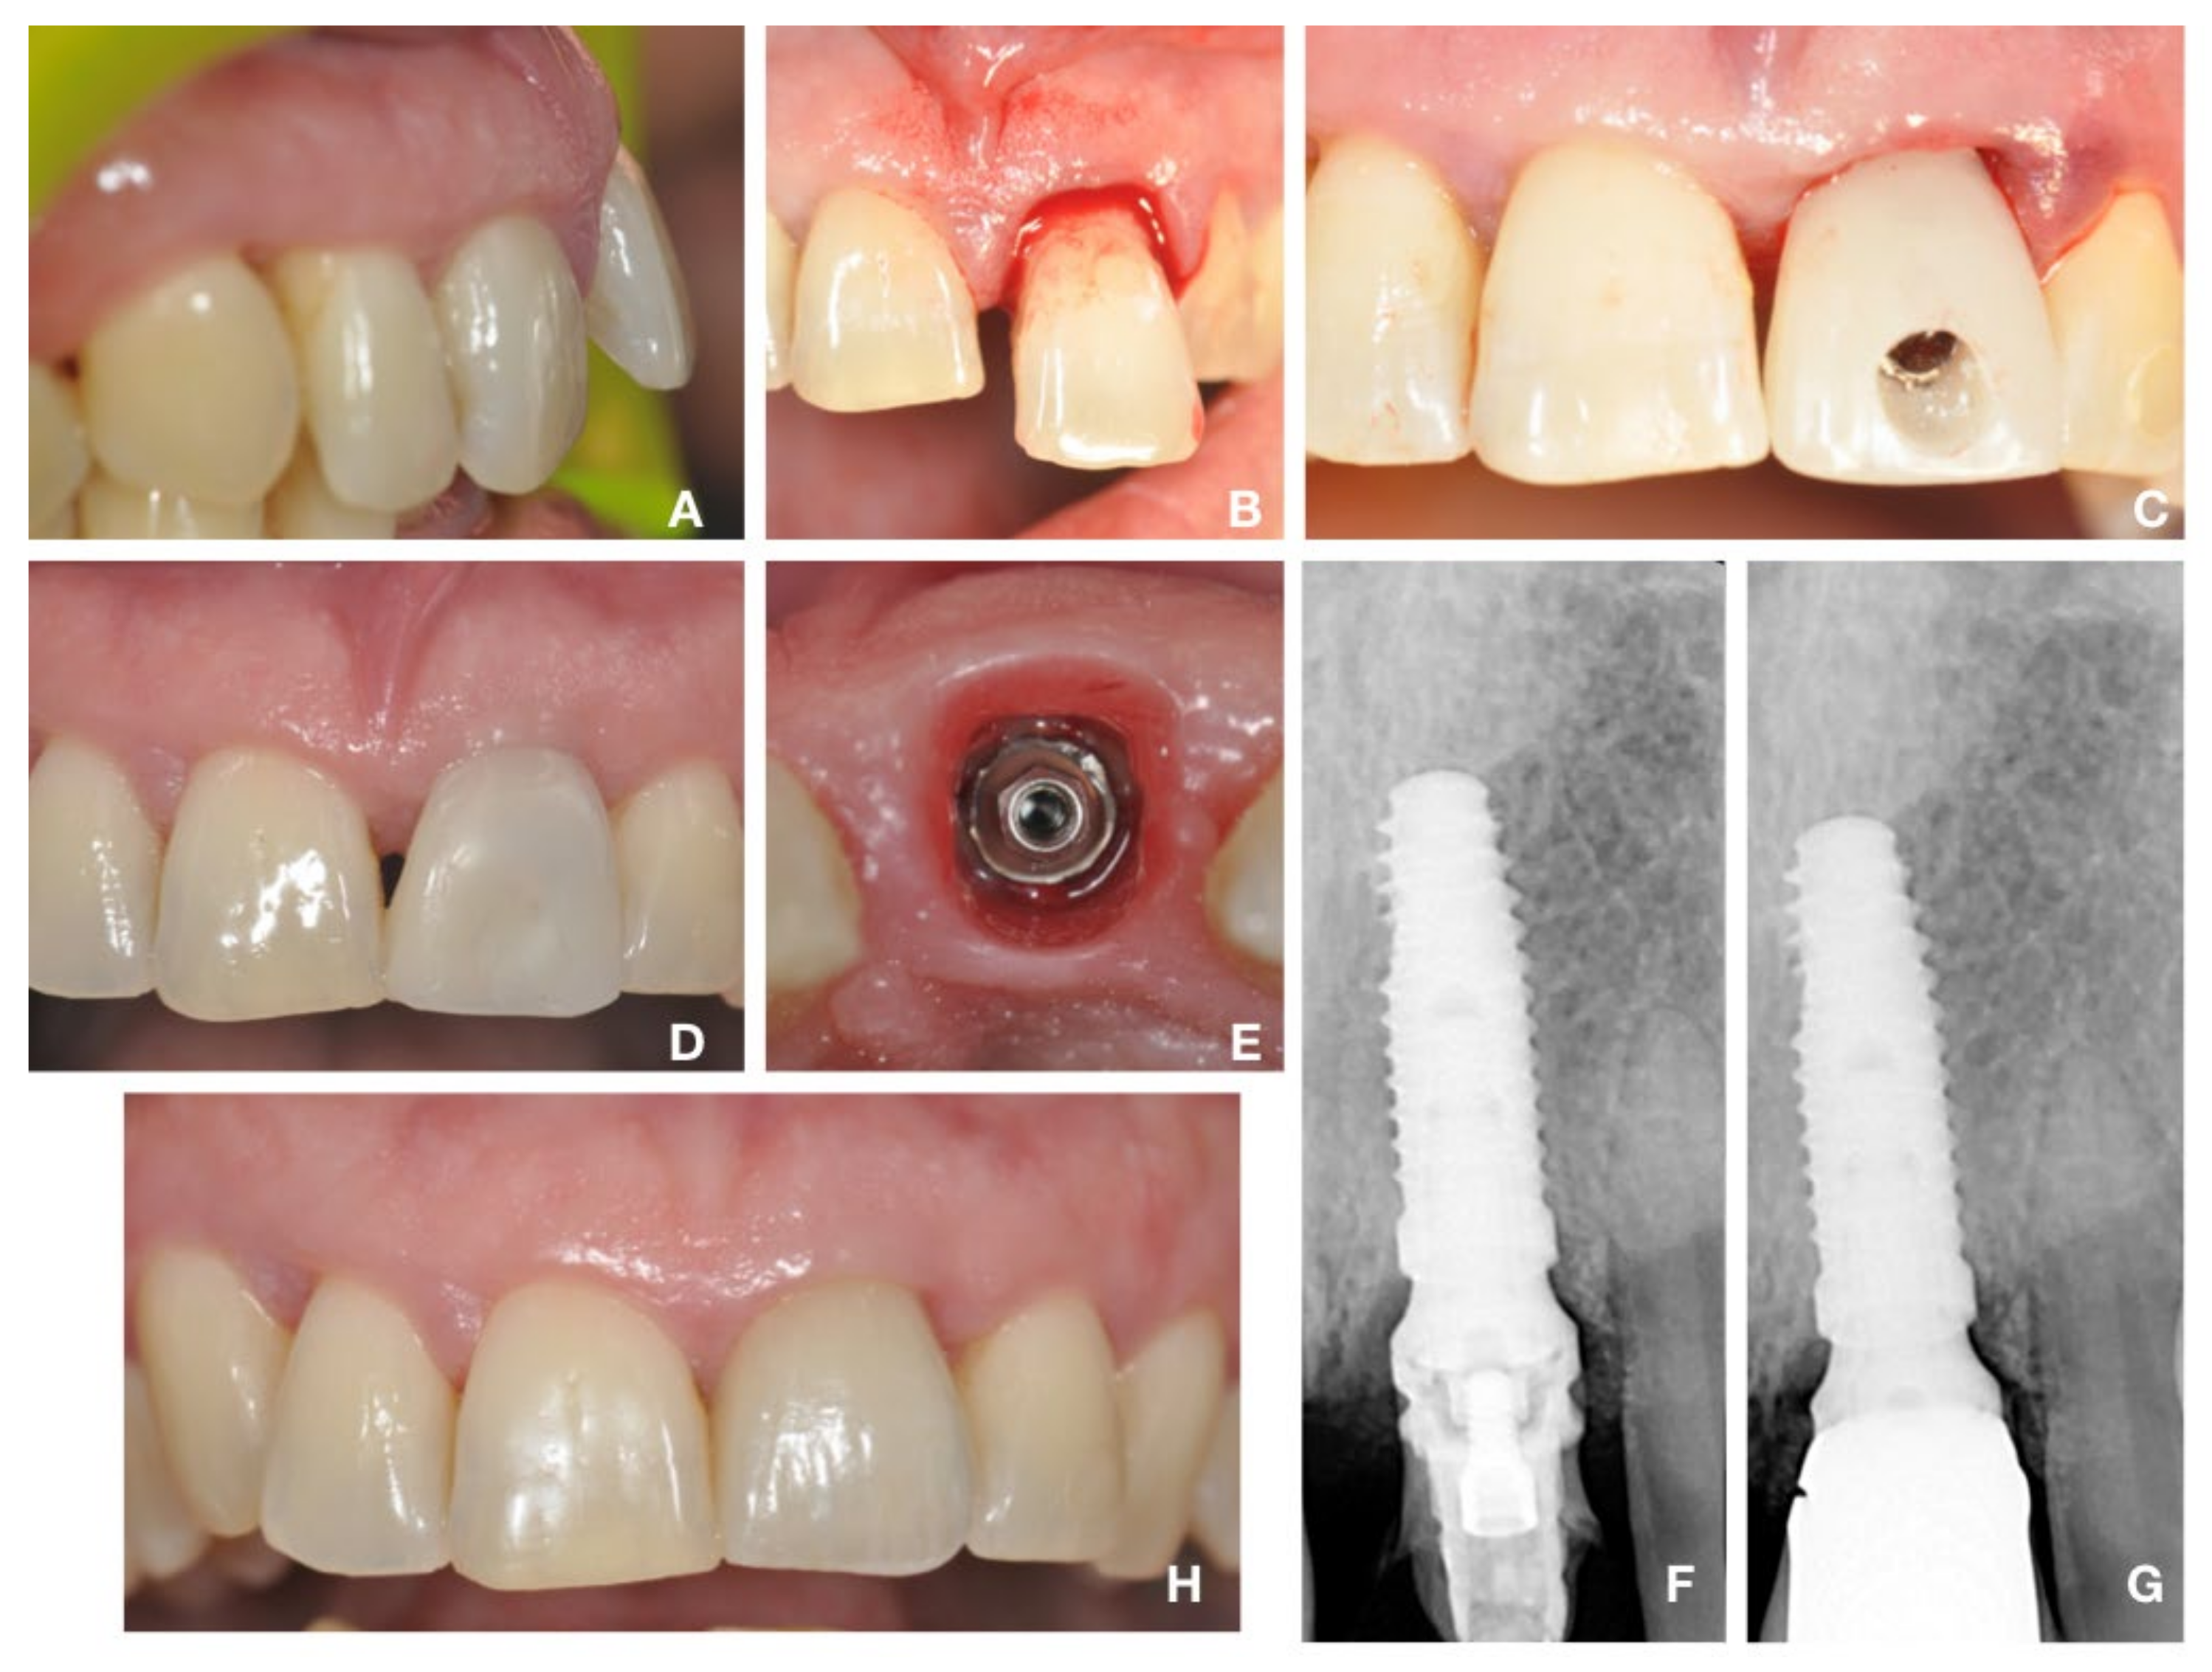

2.3. Surgical Protocol: “Biological Oriented Immediate Loading” (B.O.I.L)

2.4. Prosthetic Protocol